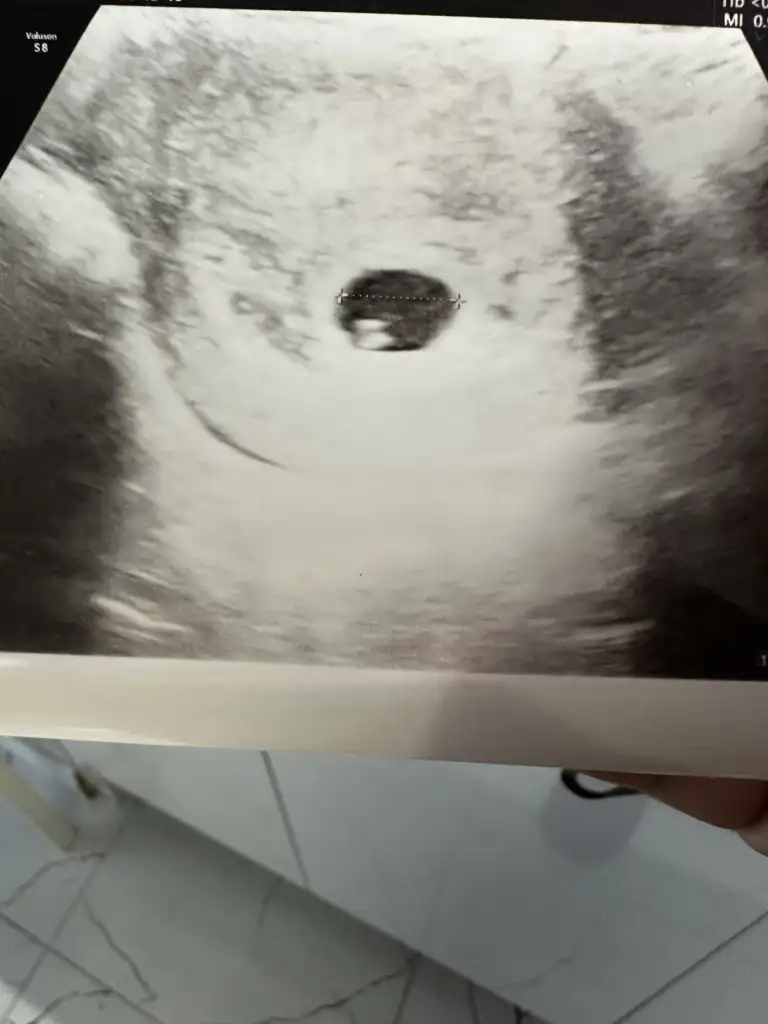

Merhaba lekelenmeniz geçti mi şu an ne durumdasınız aynı şeyleri yaşıyorum maalesefBugün 6+2 ile keseyi gördük karından.

Neredeyse 1 haftadır kahverengi lekelenmem devam ediyor az miktarda, progestan kullanmaya devam ediyoruz.

Kanama alanı görmedi doktor ama bakalım,

Haftaya kalp atışı için çağırdı